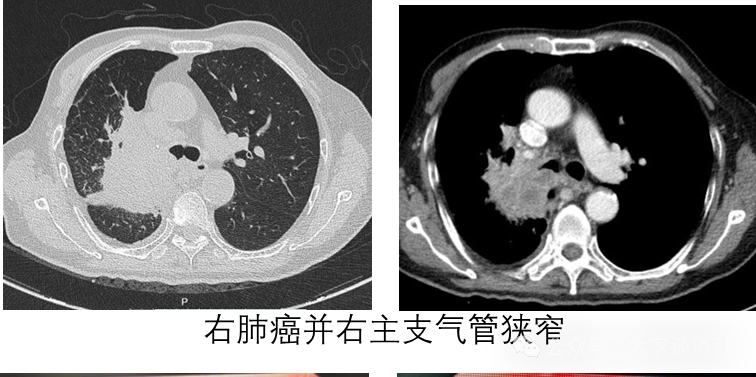

80岁的老先生因胸闷不适就诊浦东医院,经检查发现右肺上叶占位,考虑“肺癌”伴阻塞性肺不张,胸外科王冬冬医生评估后考虑患者高龄、晚期肿瘤无法进行手术治疗。经呼吸与危重症医学科张子强主任充分评估病情后决定联合一种全新的治疗方案——经支气管镜引导下PTS(甲苯磺酰胺注射液)局部化学消融治疗

在支气管镜引导下,首次支气管镜下可见肿瘤组织已堵塞右主支气管,狭窄超过90%,且病变累及范围广泛(超过3cm)。张子强主任经支气管镜冷冻冻取部分肿瘤组织后,将PTS药物注射至剩余瘤体内部,2日后行支气管镜检查可见右主支气管可见较多肿瘤坏死组织,予以清理,并为患者进行第二次PTS治疗,隔日再次通过支气管镜检查可见右主支气管肿瘤进一步坏死,右主支气管管腔逐渐恢复通畅。治疗后,右主支气管管腔从狭窄大于90%到通畅>90%,患者胸闷症状得到明显缓解,日常活动基本不受限制。结合全身肿瘤治疗后,患者顺利出院。